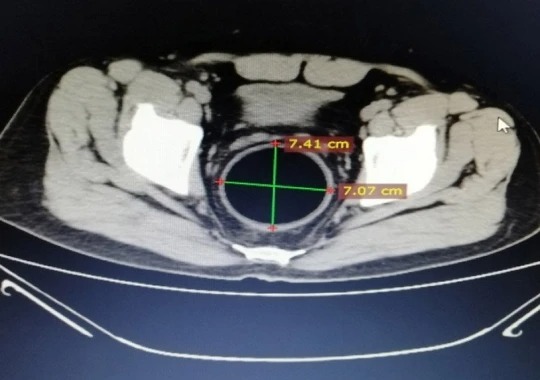

وأظهر الفحص بالتصوير المقطعي المحوسب، أن الكرة كانت أعرض من مخرج الحوض، وفحص الأطباء المريض وقالوا إنه بخير ومستقر ومتعاون واكتشفوا خدوشًا حول فتحة الشرج.

واستخدم الأطباء الأشعة السينية والتصوير المقطعي المحوسب على البطن لتحديد موقع الكرة، ولكن محاولات إزالتها فشلت، لذلك تم حجز استخراجها في صباح اليوم التالي.